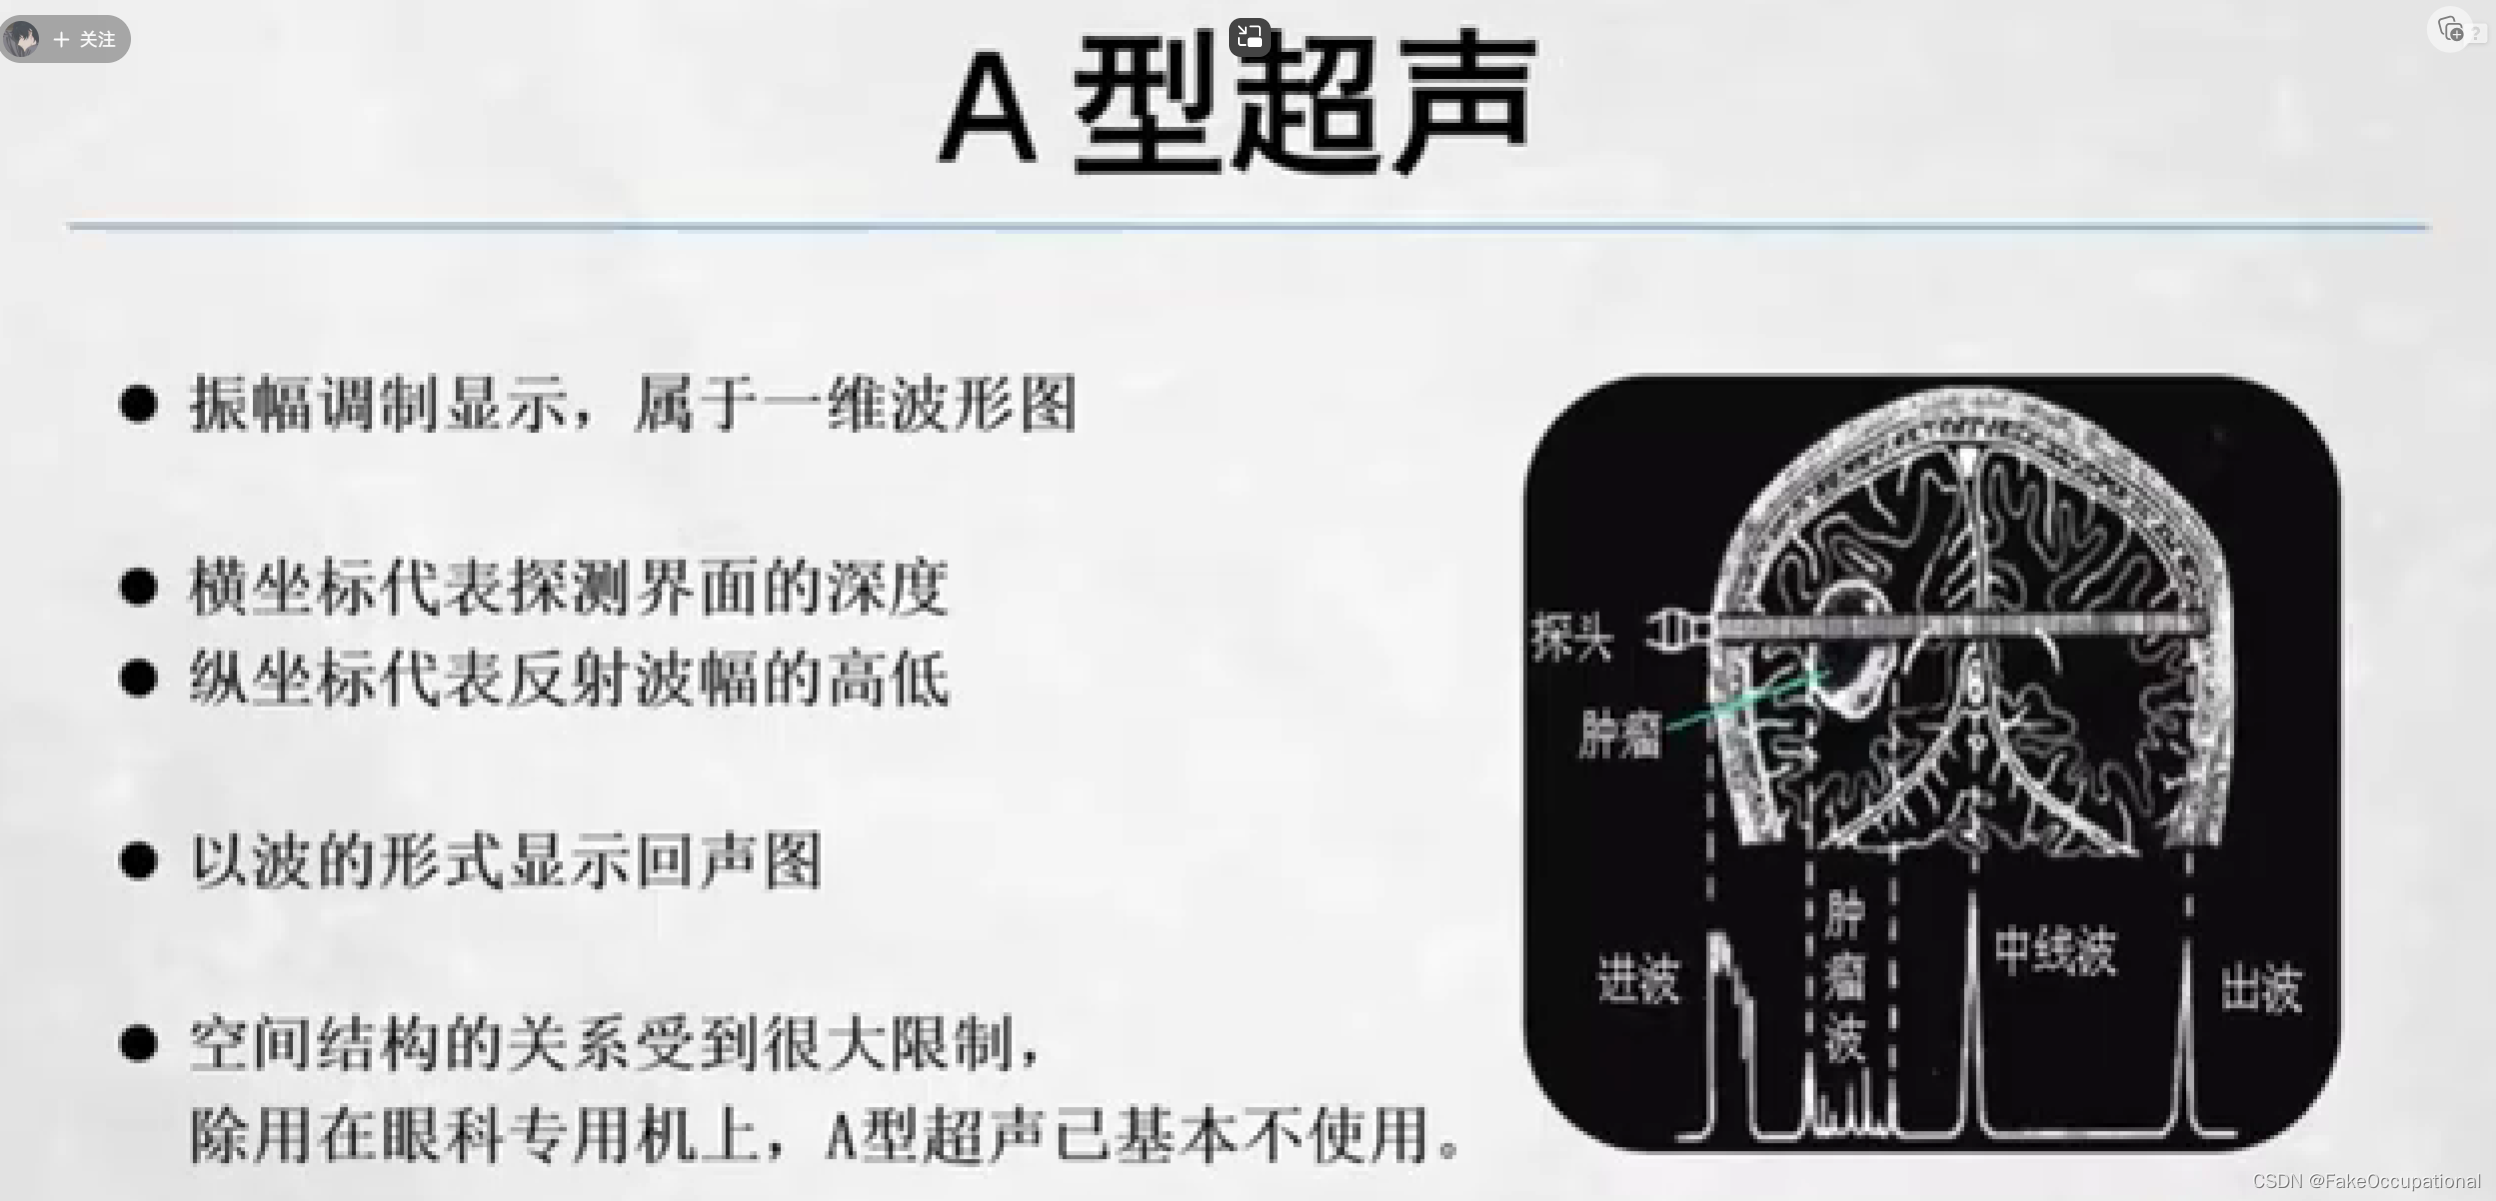

超声成像方法包括A型,B型,M型,D型(频谱多普勒,多普勒血流成像)。